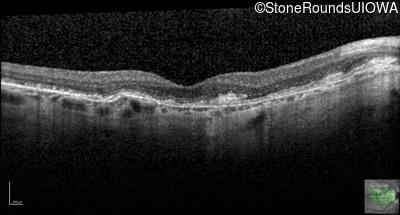

Optical Coherence Tomography - Left - 20/25 +3

Exemplar / OCT Stack